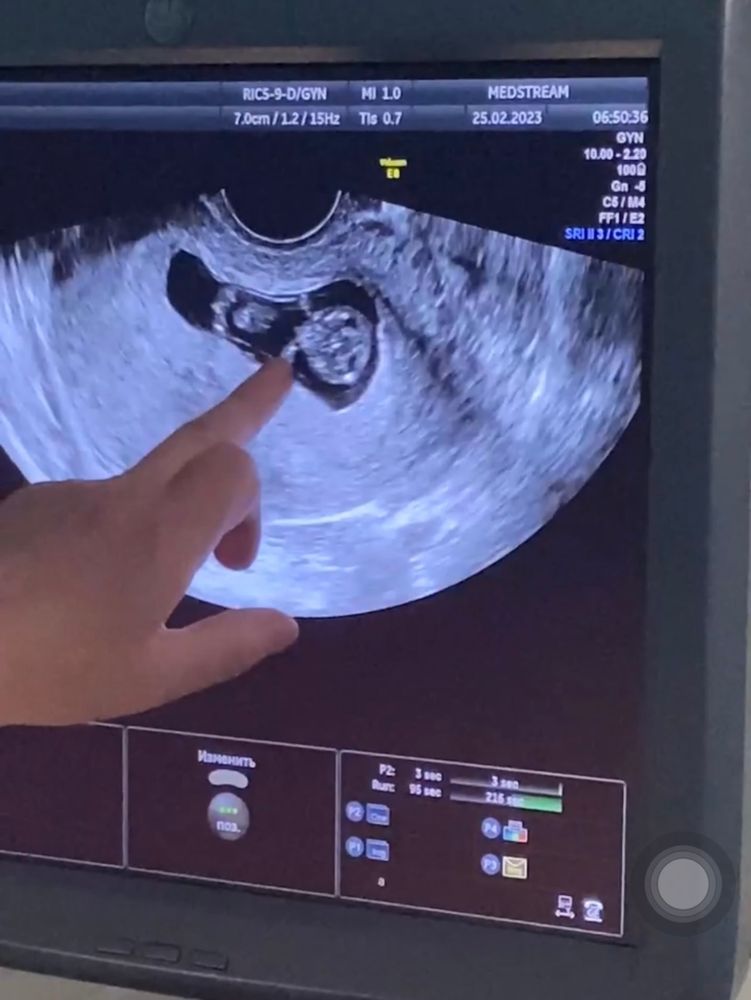

исутствовала на узи

Присутствовала на узи 118 фотографий